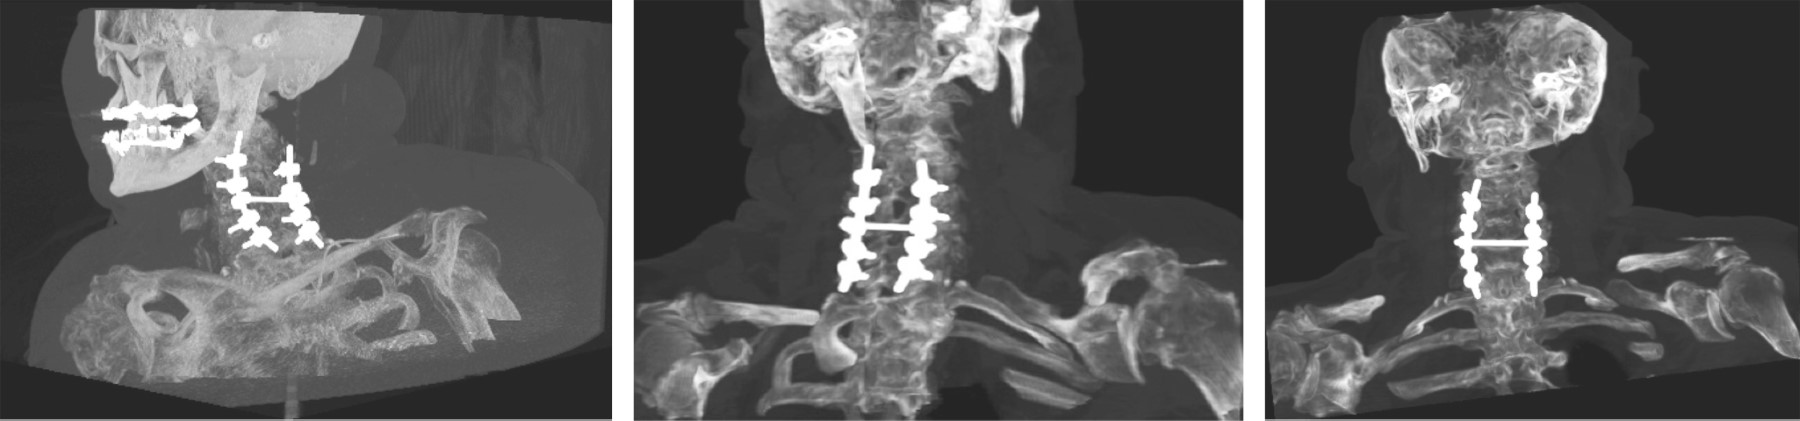

Diffuse idiopathic idiopathic skeletal hyperostosis (DISH), or Forestier's disease is a rare disease of unknown etiology. It is a systemic condition in which ossification of the anterolateral sides of at least four contiguous bodies, calcification of ligaments and entheses develops and is accompanied by spinal pain predominantly in the thoracic spine. In this case report we present a 70-year-old female patient presenting with DISH with complete spinal cord injury from c7 to distal on ASIA A scale following a fall from her own plane of support managed surgically with posterior cervical approach and instrumentation of lateral masses and decompression with good clinical evolution and partial clinical recovery to ASIA C.

Figure 1